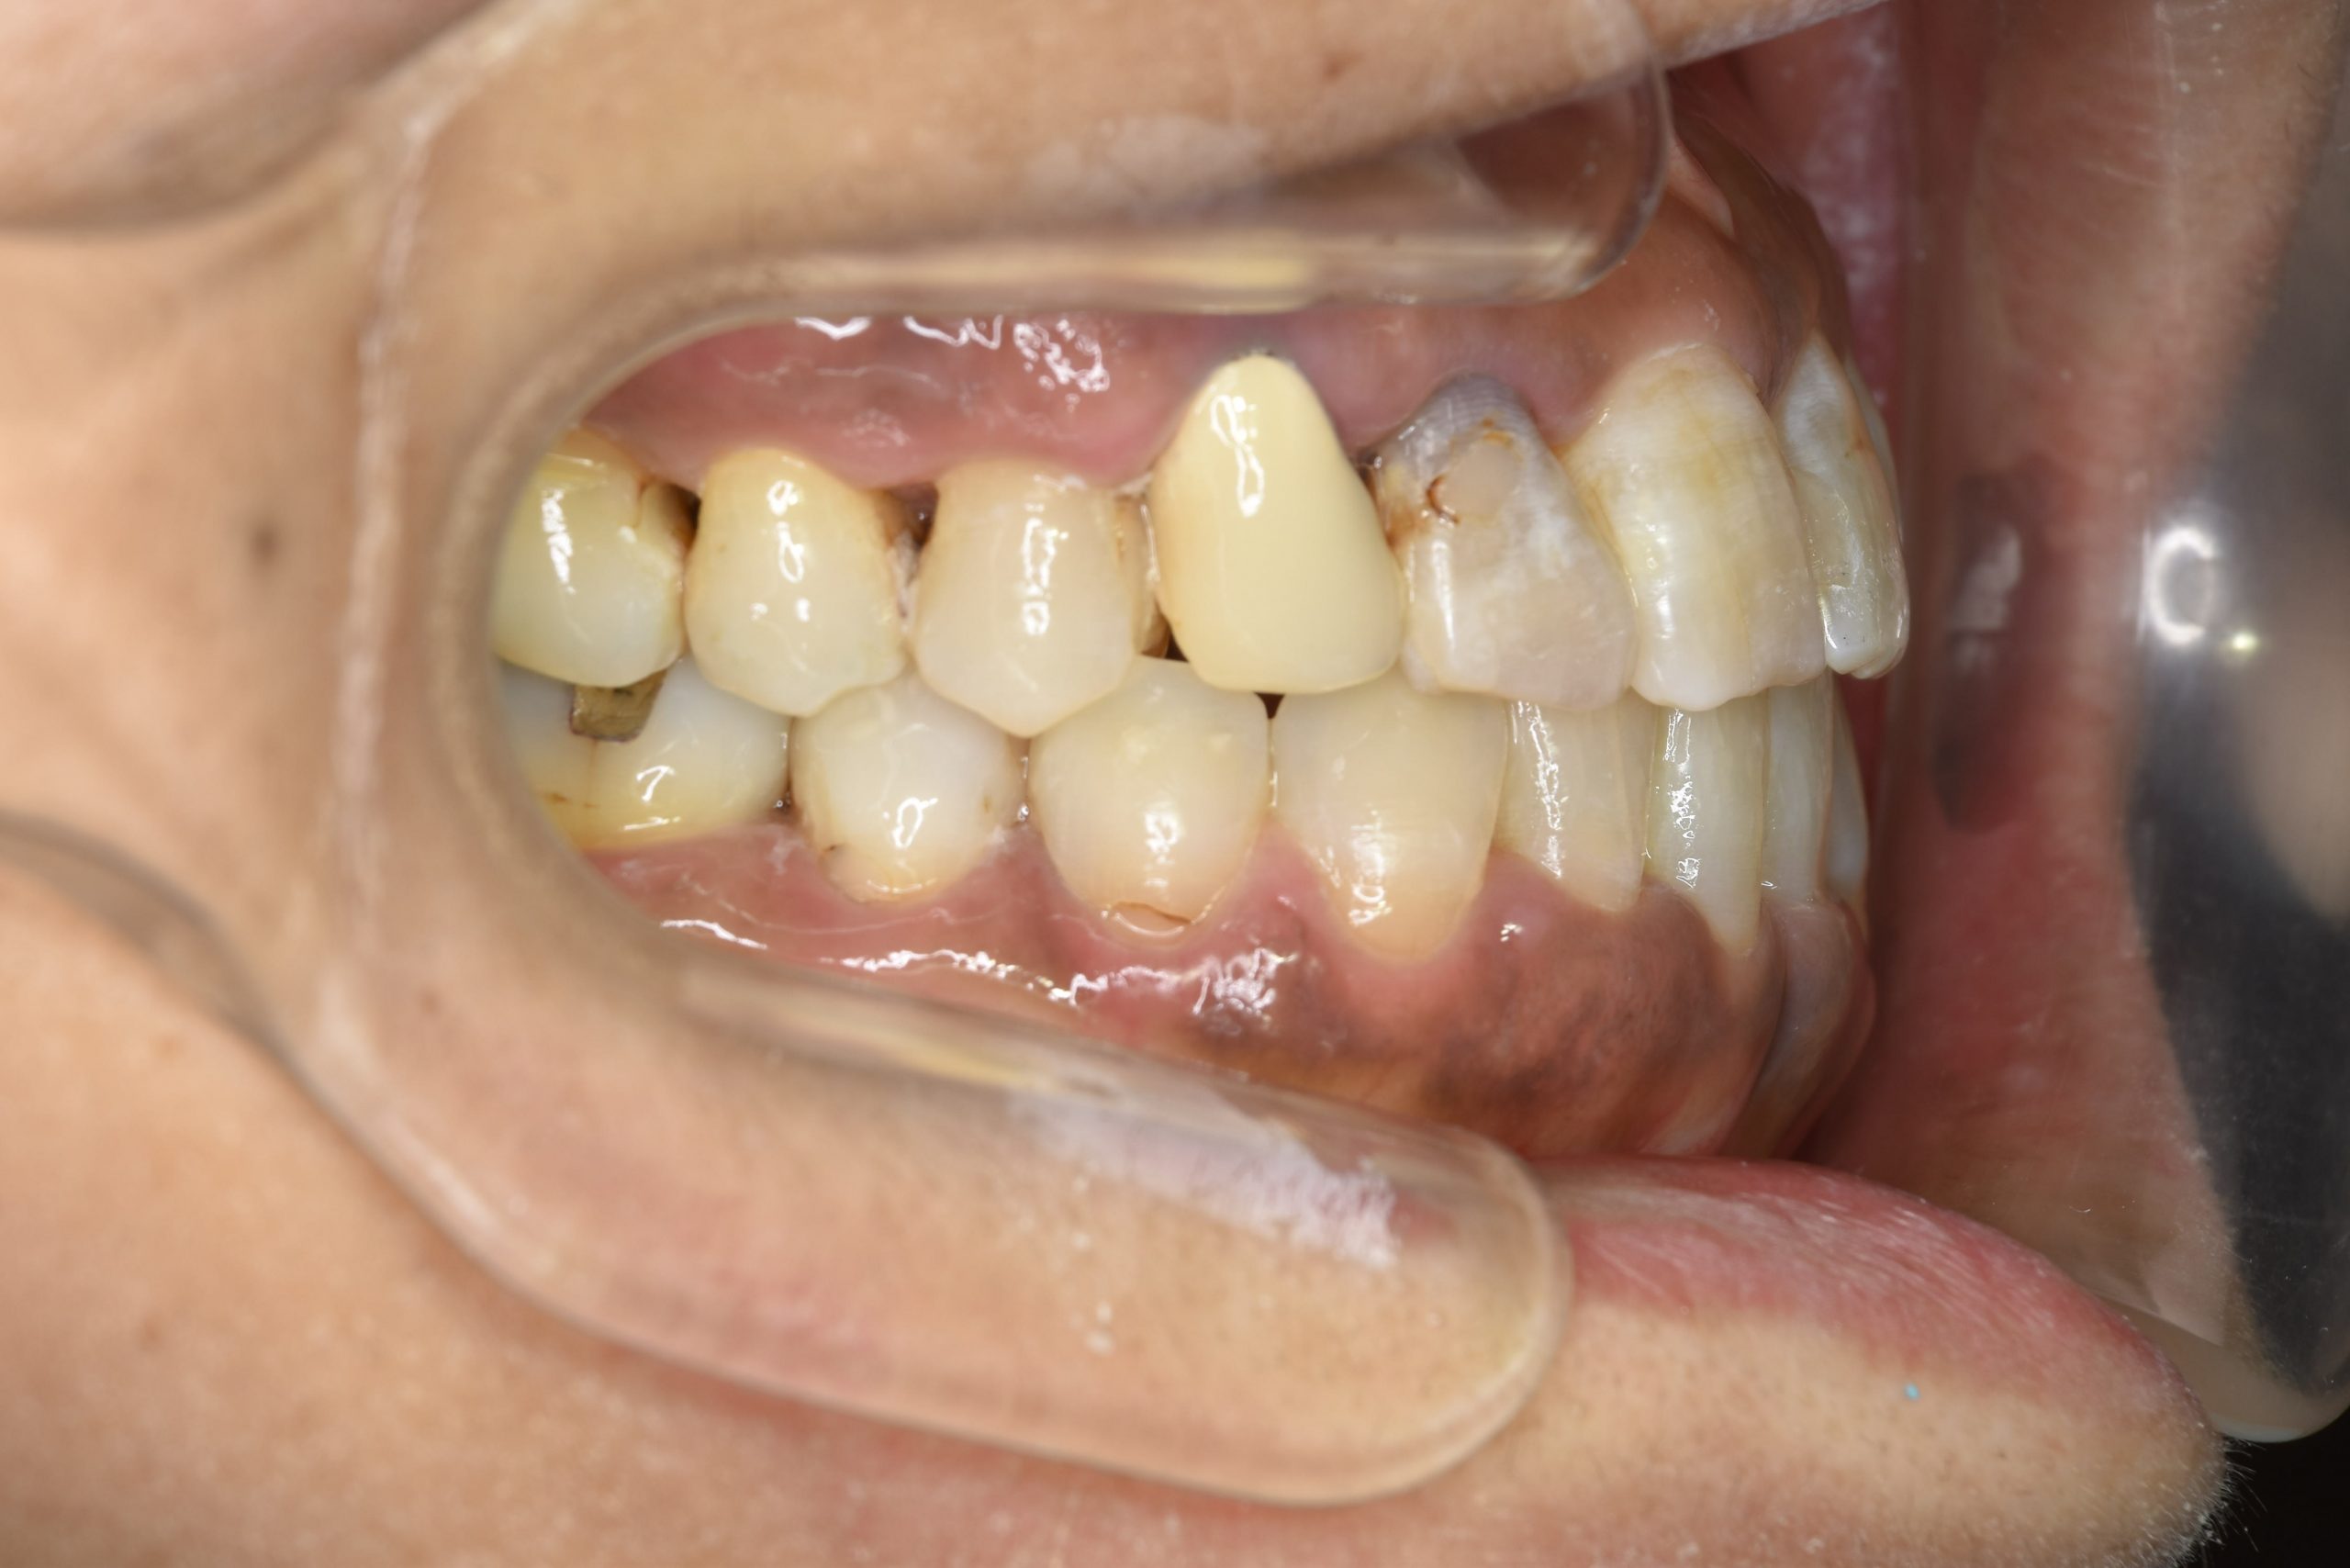

ビフォー

ワイヤー矯正治療|症例_588

主訴 かみ合わせ ※抜歯あり

施術内容 MSEと下顎リンガルアーチを用いて上下顎骨を拡大した。

その後下顎前歯を1本抜歯してマルチブラケット装置を用いて

歯牙を配列し良好な咬合を獲得した。側貌は改善した。